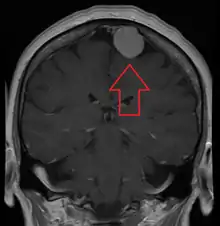

Diagnosis

Meningiomas are visualized readily with contrast CT, MRI with gadolinium,[22] and arteriography, all attributed to the fact that meningiomas are extra-axial and vascularized. CSF protein levels are usually found to be elevated when lumbar puncture is used to obtain spinal fluid. On T1-weighted contrast-enhanced MRI, they may show a typical dural tail sign absent in some rare forms of meningiomas.[17]